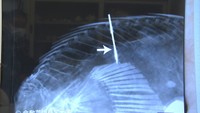

人魚のミイラに「哺乳類とも魚類とも異なる特徴」 研究チームが中間報告 岡山

生物学が専門の、倉敷芸術科学大学・加藤敬史教授